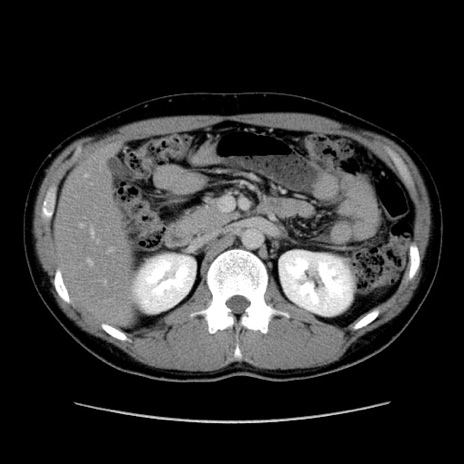

症例36(横断像)

【症例】20歳代 男性

【主訴】心窩部痛

【現病歴】今朝より上腹部痛あり。一旦軽快していたが再度出現したため救急要請。昨日夕に白身の魚を含む刺身を食べた。

【身体所見】BP 136/89mmHg、HR 74/min、BT 37.0℃、腹部:膨満、軟、心窩部に圧痛あり。反跳痛なし、筋性防御なし、腸雑音やや亢進あり。

【データ】WBC 17700、CRP 0.48